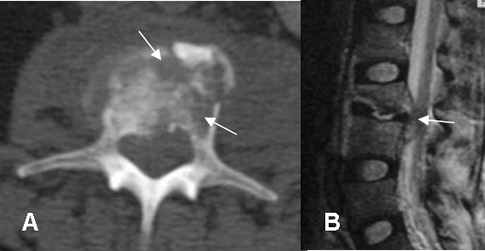

Fig 49. Osteomielitis TBC.

A: TAC axial. Igual paciente anterior. Lesiones líticas en el cuerpo de L3.

B: RM sagital en T2. Pérdida de altura en el cuerpo vertebral, de predominio en la parte anterior y colección epidural asociada, que comprime el saco dural.